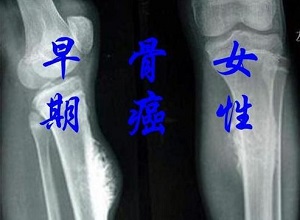

日常生活中我们应该注意骨癌的发生,患者患此病后会有剧烈疼痛。为了减轻患者的疼痛,我们应该进行合理的治疗。这种疾病有很多因素,我们应该注意预防,保持良好的态度,注意休息。那么,预防骨癌的方法是什么呢?下面一起来了解一下。

X线。镭。氢。锶。放射性同位素等电离辐射可以在体内或体外辐射,这会诱发骨癌的发生。尤其是在青少年骨骼发育期间,应尽量减少和避免放射性辐射。